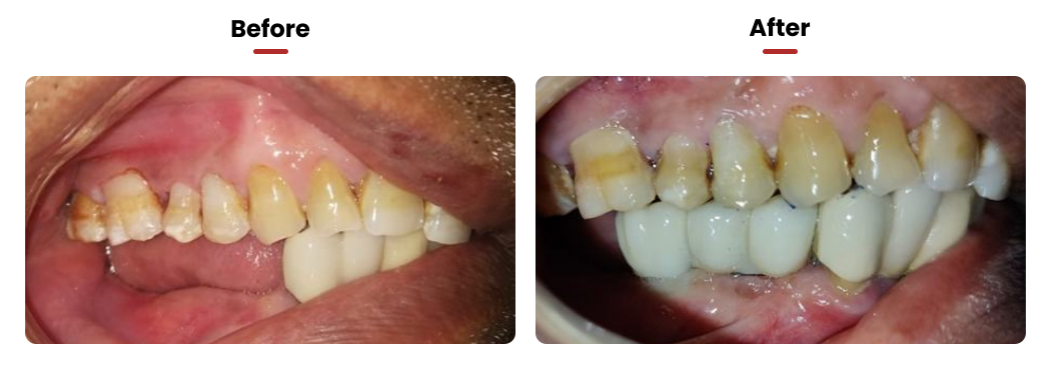

• This technique stands out as the optimal method for replacing natural teeth. It notably enhances the aesthetic appeal of one’s smile, particularly in areas where new teeth are visible. As a result, it boosts confidence in smiling and speaking.

• Another significant advantage of this approach is its role in bone preservation. It contributes to improved periodontal health, leading to healthier gums and overall enhanced oral health compared to the state with missing or loose teeth

Dental Implant Restoration in Lower Right Jaw

• The patient experienced difficulty in chewing due to missing teeth in the lower right section of the jaw. To address this, two implants were placed in the affected area, and subsequently, three crowns were